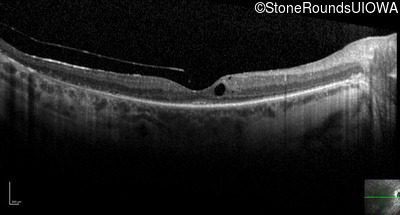

Optical Coherence Tomography - Left - 20/80 -2

Exemplar / OCT Stack